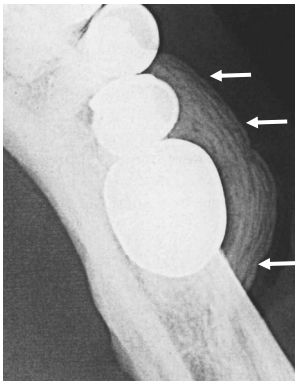

67 下列所附咬合片(occlusal film)中,對箭頭所指之放射線影像,最適切之描述為何? (A)洋蔥皮狀影像(onion-skin appearance) (B)陽光線狀影像(sun-ray appearance) (C)羊毛棉花狀影像(cotton-wool appearance) (D)毛玻璃狀影像(ground-glass appearance)